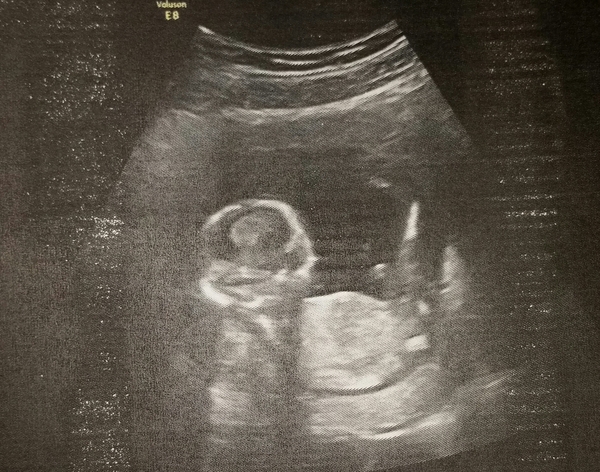

Well, had another scan today and test results for t21. Scan looks good and results were negative GrinGrin

Still holding my breath a little for the 20 week scan but so far so good. Dates have changed again though. In line with my LMP and the measurements taken today I'm a week further than last thought, so now 14+4. The baby has big feet Shock